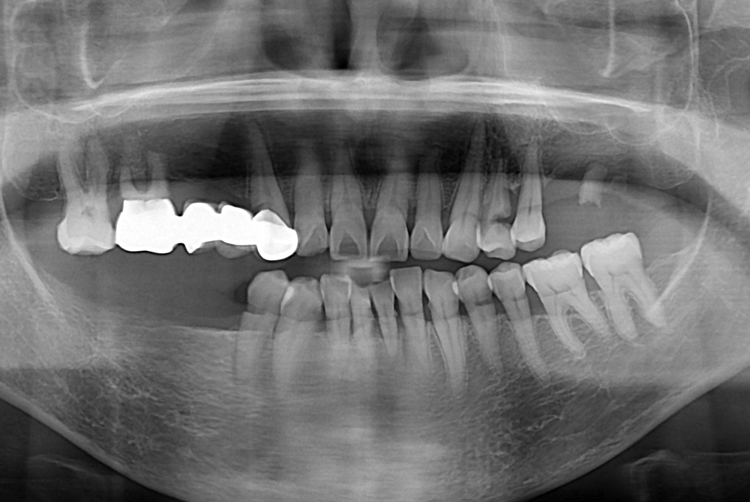

[임플란트] 어금니 임플란트

치료후 : 2019-07-30

세종치과는 많은 환자와 다양한 케이스를 바탕으로

항상 편안한 임플란트 수술을 제공하고자 노력하고,

오래동안 튼튼히 쓸 수 있는 임플란트 수술을 가장 큰 목표로 삼고 있습니다.